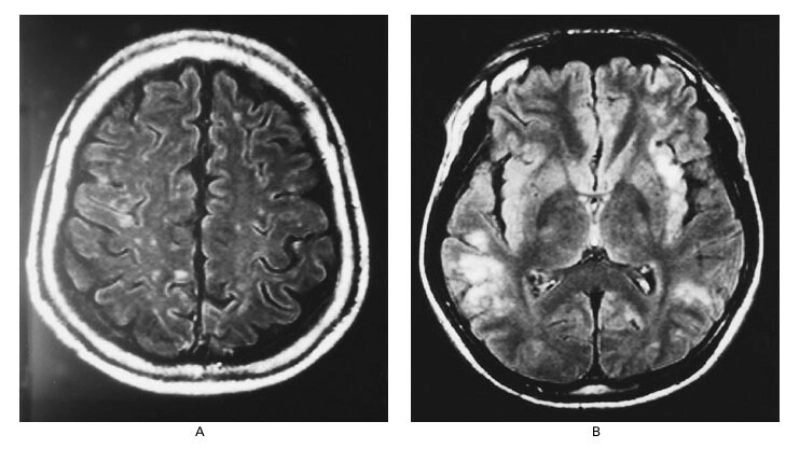

Image description of Nipah Virus Encephalitis

Nipah Virus Encephalitis is a rare but deadly viral infection transmitted from bats or animals to humans. It primarily affects the brain, causing severe neurological and respiratory symptoms. Awareness and prevention are crucial to controlling outbreaks.